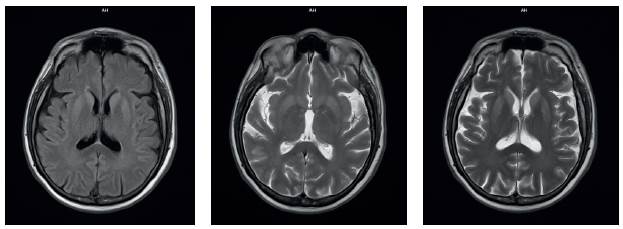

Los estudios paraclínicos solicitados, que incluyeron biometría hemática, química sanguínea, electrolitos séricos, pruebas de función hepática y renal, así como el citoquímico del líquido cefalorraquídeo (LCR), se encontraron normales. La resonancia magnética nuclear (RMN) cerebral contrastada evidenció hiperintensidad en las secuencias T2 en la región anterior e inferior núcleo-basal bilateral, simétrica con restricción en la secuencia de difusión, particularmente notorio en la cabeza y cuerpo del núcleo caudado, lo que impedía tomar una biopsia cerebral (Figura 1). La gammagrafía SPECT cerebral fue negativa para áreas de hipo- o hiperperfusión asimétricas a nivel cortical y cerebeloso, las cuales no contribuyeron a seleccionar un área idónea para biopsia.

La RMN cerebral es el método más útil para el diagnóstico de Ecj, cuenta con una sensibilidad de 91-96 % y una especificidad de 92-94%, además de estar ampliamente disponible y no ser invasiva. Hay tres patrones principales de hiperintensidades en la RMN: cortical y subcortical (68 % de los casos), predominantemente neocortical (24 %) y predominantemente subcortical (principalmente estriado, con o sin cambios talámicos, 5 %) 19-23.

La prueba de referencia para el diagnóstico de ECje consta de un estudio anatomopatológico en el que se observe vacuolización característica, sin componente inflamatorio en el encéfalo. En este paciente, el estudio de los niveles de proteína 143-3 y proteína Tau en LCR sugirió fuertemente el diagnóstico, a lo cual se sumó el estado clínico del paciente y los hallazgos en la RMN. Este caso corresponde a una ECJ que presumimos es esporádica por la edad de presentación y porque no contamos con antecedentes exposicionales como cirugías, antecedentes familiares de demencia inespecífica o viajes a Europa que sugirieran otro origen de la patología priónica.